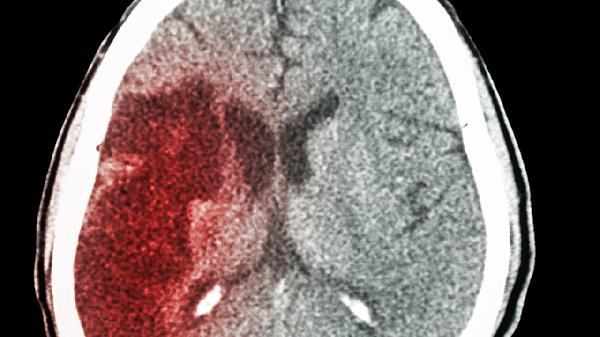

脑出血患者烦躁不睡觉可能与颅内压增高、脑组织损伤、疼痛刺激、代谢紊乱或药物副作用等因素有关。脑出血后脑组织水肿或血肿压迫可导致颅内压升高,引发头痛、意识障碍及精神症状;脑损伤直接影响情绪调节中枢时,可能出现躁动不安;部分患者因头痛或肢体疼痛难以入睡,而电解质失衡、缺氧等代谢问题也会加重烦躁。此外,治疗中使用的脱水剂、镇静药物可能产生反跳性兴奋作用。

颅内压增高是脑出血后常见病理变化,血肿占位效应和脑水肿会机械性压迫脑干网状结构,干扰睡眠觉醒周期。患者常伴随喷射性呕吐、视乳头水肿等症状,需通过甘露醇注射液或呋塞米注射液降低颅内压。脑组织损伤若累及边缘系统或前额叶皮层,可能破坏情绪调控功能,表现为易激惹、攻击性行为,此时需密切监测生命体征,必要时使用右美托咪定注射液镇静。